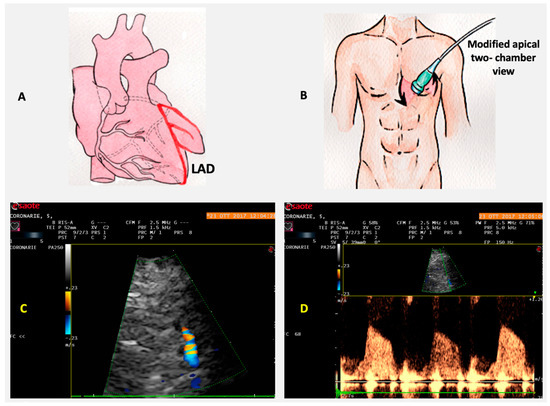

6. Coronary Flow Reserve

Role of CFR in IHD

- Gan, L.-M.; Svedlund, S.; Wittfeldt, A.; Eklund, C.; Gao, S.; Matejka, G.; Jeppsson, A.; Albertsson, P.; Omerovic, E.; Lerman, A. Incremental value of transthoracic doppler echocardiography-assessed coronary flow reserve in patients with suspected myocardial ischemia undergoing myocardial perfusion Scintigraphy. J. Am. Heart Assoc. 2017, 6, e004875. [Google Scholar] [CrossRef]

- Haraldsson, I.; Gan, L.-M.; Svedlund, S.; Wittfeldt, A.; Råmunddal, T.; Angerås, O.; Albertsson, P.; Matejka, G.; Omerovic, E. Non-invasive evaluation of coronary flow reserve with transthoracic Doppler echocardiography predicts the presence of significant stenosis in coronary arteries. Int. J. Cardiol. 2014, 176, 294–297. [Google Scholar] [CrossRef]